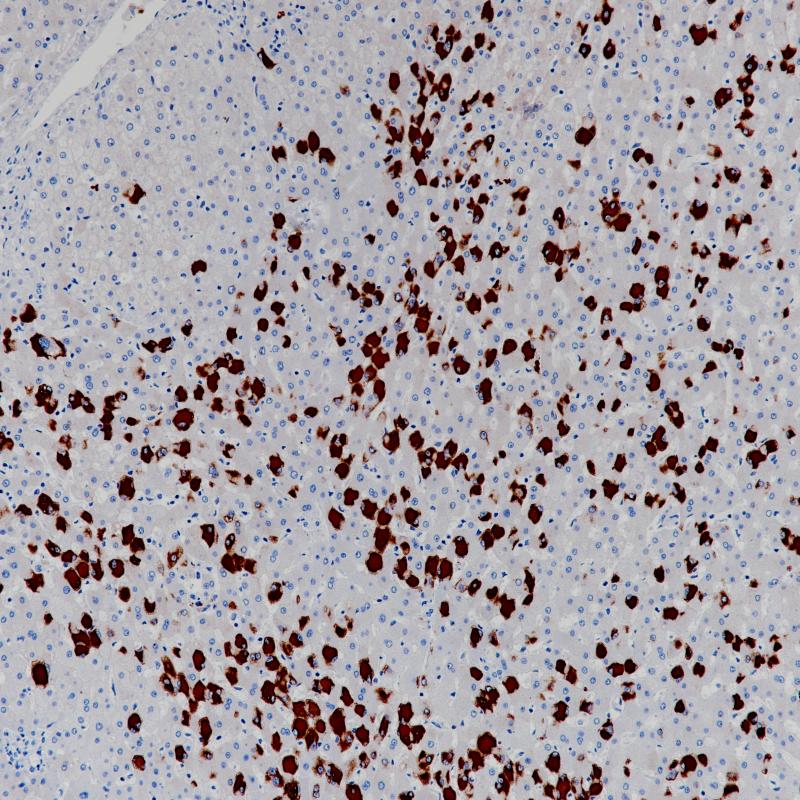

HBV感染肝脏HBSAg(BP6224)染色-2

乙肝表面抗原(HBsAg)是乙肝病毒表面的糖蛋白。乙肝感染后,HBsAg作为第一病毒标志物出现。患者感染乙型肝炎病毒2到6个月后,HBsAg可以在其血液、唾液、乳汁,汗水,泪水,鼻咽分泌物、精液和阴道分泌物中检测到。HBsAg抗体主要用于乙肝病毒的诊断。

阳性对照

HBV感染肝脏

亚细胞定位

细胞质